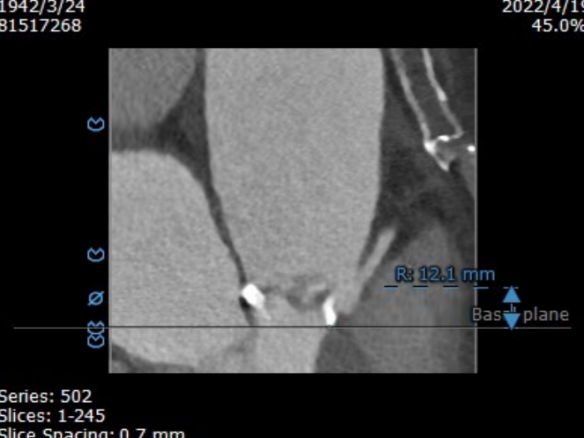

主动脉瓣瓣环周长85.4mm,周长径27.2mm,LVOT 28.1mm,STJ 29.4mm。CT数据分析显示该患者为Type1型二叶瓣,瓣叶重度钙化且增厚,主要分布于无冠瓣叶,左冠窦有团状钙化并延伸至左室流出道,HU850:957mm²。

左冠开口高度13.0mm,右冠开口高度16.5mm,双侧冠脉开口未见明显附壁钙化,结合瓦氏窦宽度和瓣叶长度综合判断冠脉阻挡风险较低。